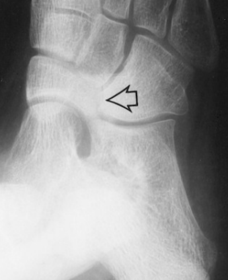

What is this? | Os subtibiale |

What foot type does this calcaneal inclination angle indicate? | Pes cavo-varus |